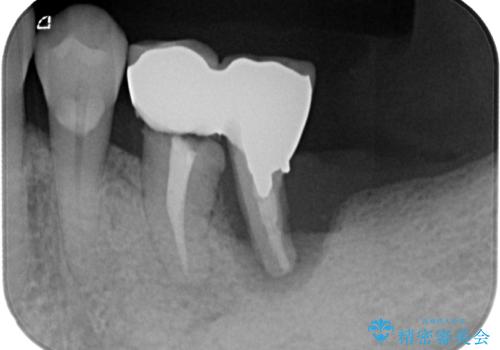

- 右上下の奥歯がむし歯でしみたり痛んだりするとのことで来院された患者様です。

下顎の奥歯は強い痛みを感じており、既に歯髄に不可逆的な炎症が起きていると診断されたため、根管治療の後にセラミッククラウンにて補綴治療を行うこととしました。

下顎のむし歯は歯肉の中にまで及んでいたため、一部歯槽骨を削除し、歯肉縁上に健全歯質が位置するよう外科処置を併用しました。